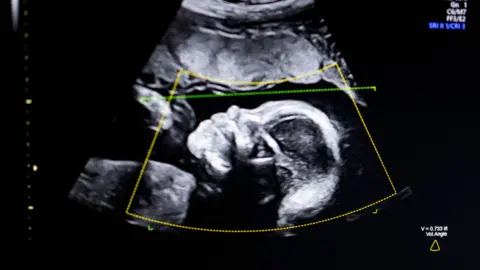

Getty Images

Private clinics often offer reassurance or sexing scans before the standard NHS anomaly scan which is normally offered between 18 and 21 weeks into the pregnancy